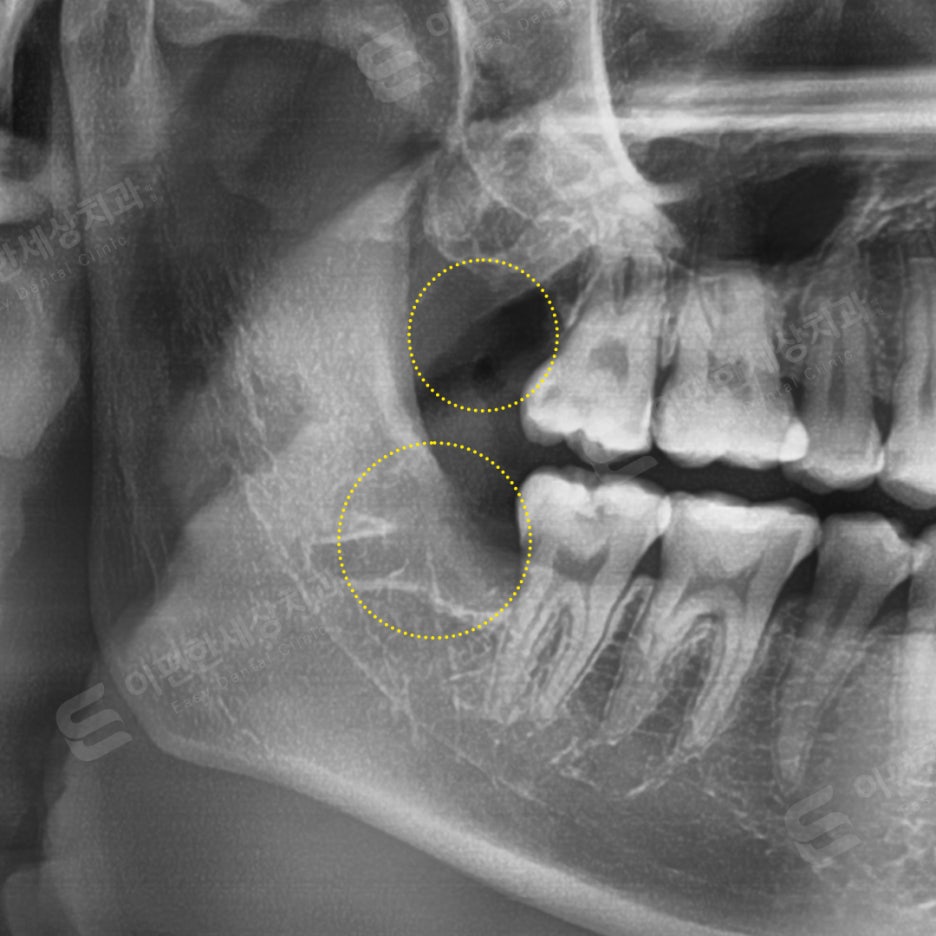

촬영 일자 24. 02. 17

인터넷 검색 후 내원, 당일 발치 케이스

#48 복잡매복 발치

치아 뿌리와 신경관 가까워 보여

CT 촬영 후 발치

#18 일반 발치